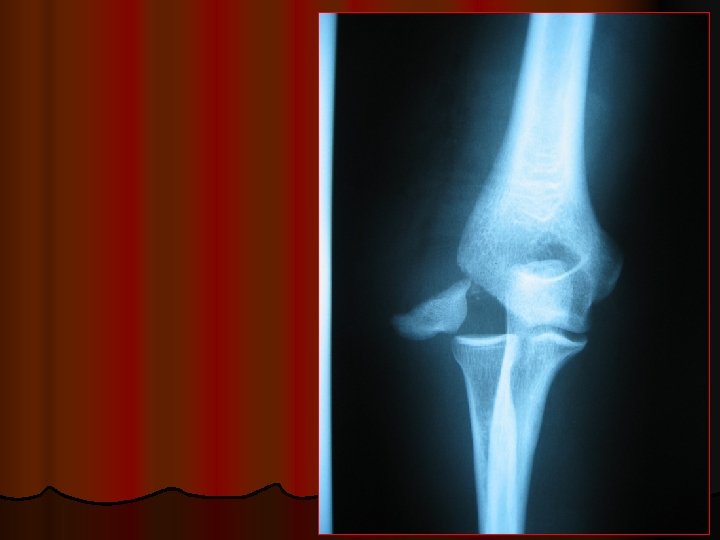

INJURIES AROUND THE ELBOW <<7 4 l l l l 1 - SUPRACONDYLAR FRACTURE 2 - DISLOCATION ELBOW 3 - FRACTURE OLECRANON 4 - FRACTURE HEAD RADIUS 5 - FRACTURES OF HUMERAL CONDYLES 6 - EPICONDYLE FRACTURE 7 - PULLED ELBOW 3 >>2 5 6 1 5

DISLOCATION ELBOW POSTERIOR

PO ST ER IO R rior Ante POSTERIOR DISLOCATION